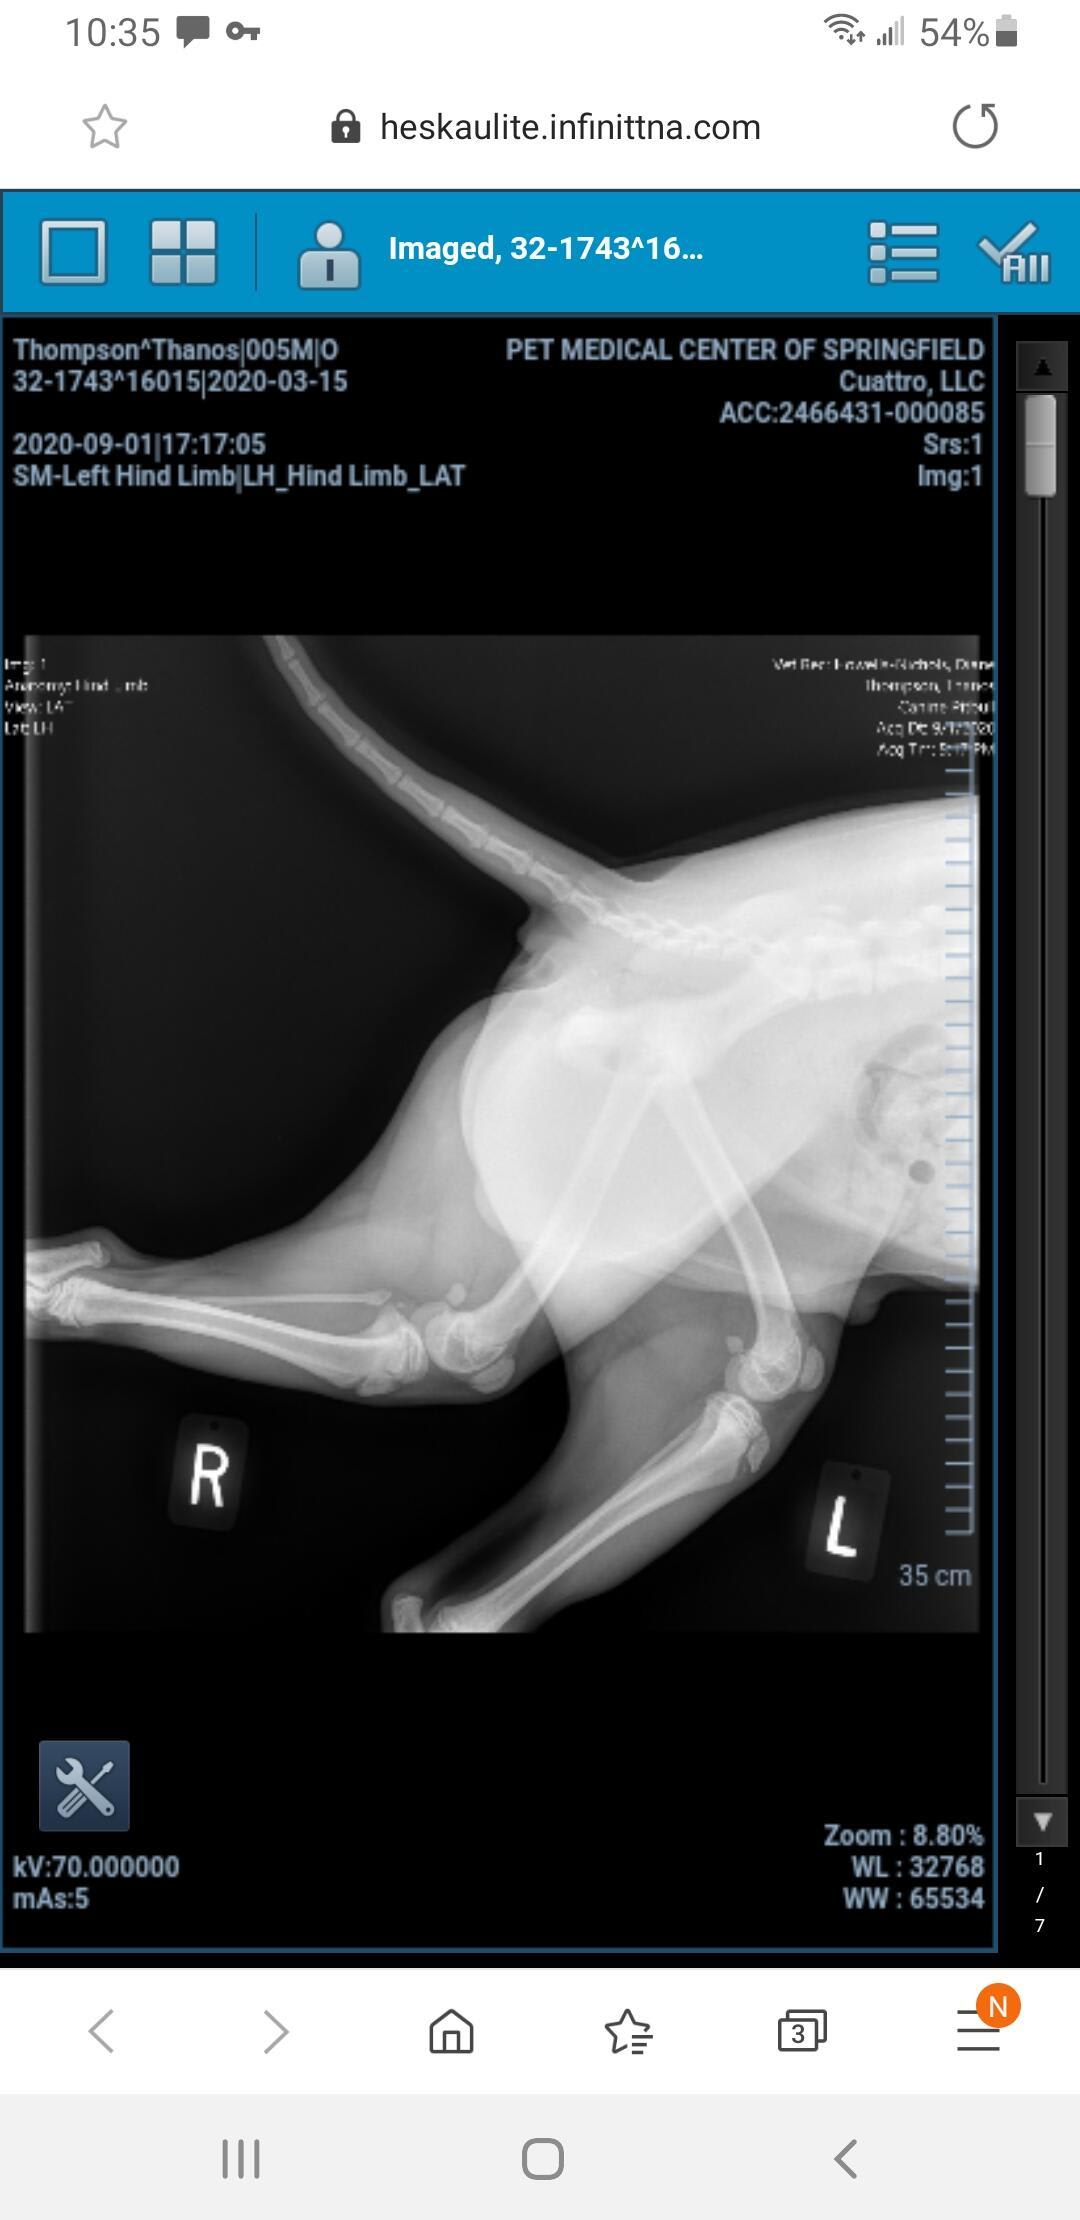

My dog jumped for a water bottle and landed wrong. Is he injured?

Pet's info: Dog | American Pit Bull Terrier | Male | unneutered | 5 months and 18 days old | 37 lbs

Dog jumped up for water bottle and landed wrong

Hello. Most likely your veterinarian recommended surgery to repair the fracture, & I would confirm that that is the best way to go. So sorry this has happened to Thanos, but glad you are looking out for him. Thanks for contacting Petco Pet Education Center, formerly Petcoach.